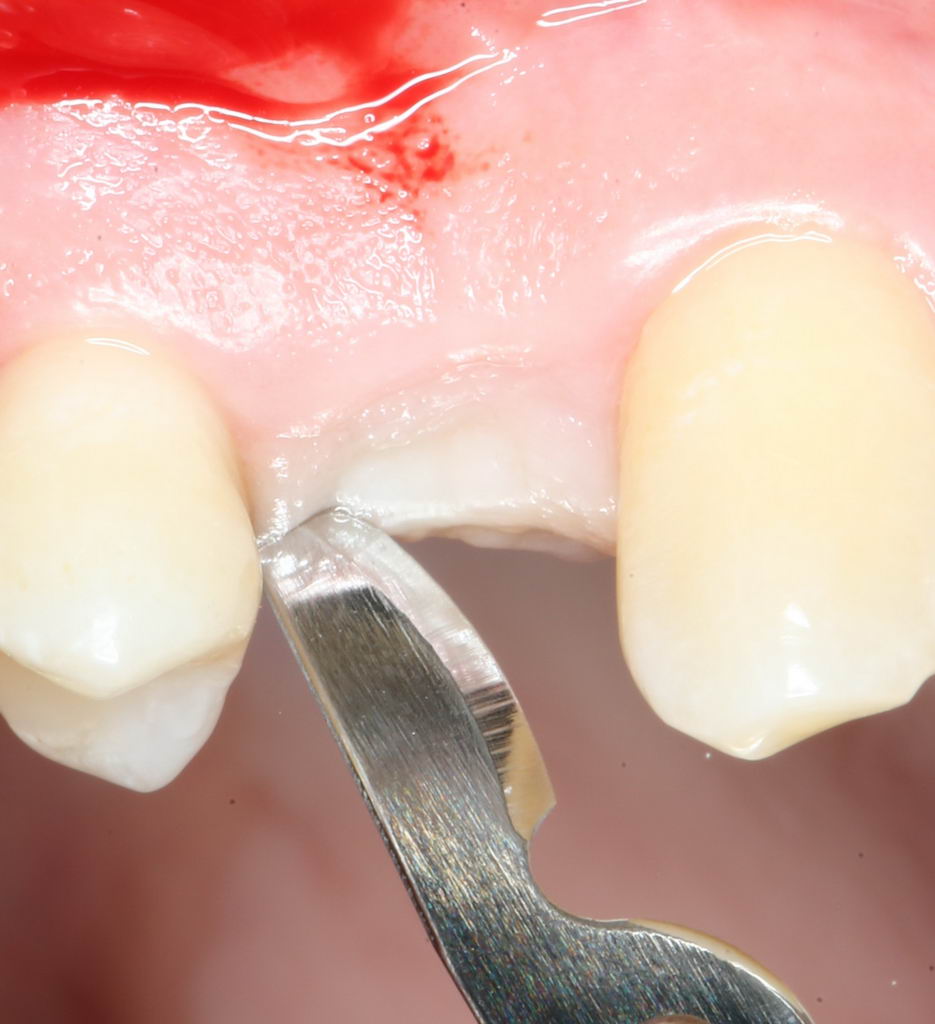

Разрез и скелетирование альвеолярного гребня.

Разрез и скелетирование делаются, исходя из двух взаимоисключающих нюансов: с одной стороны, разрез должен быть минимально травматичным, с другой — обеспечивать хороший обзор:

Мы немного смещаем разрез в сторону нёба для того, чтобы потом нормально сформировать десну. Это видно на правой фотографии выше.